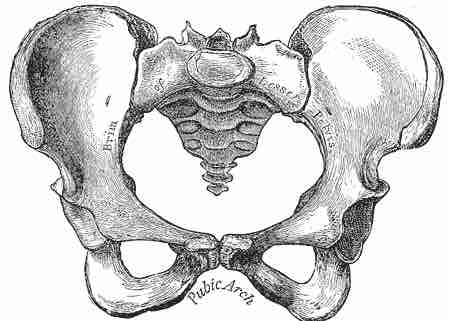

The Female Pelvis

The female pelvis is wider than that of the male, as can be seen by the greater than 90 degree angle of the pubic arch.